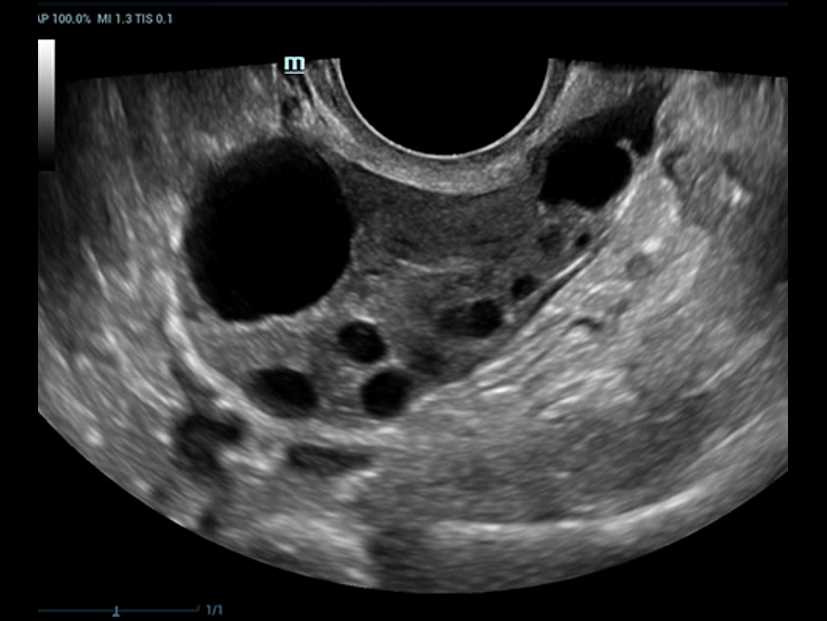

Smart FLC

Smart FLC rileva automaticamente il numero di follicoli e calcola ogni volume a partire da un'immagine volumetrica ovarica 3D, garantendo la valutazione accurata dei follicoli, in particolare per gli esami IVF.

Follicoli